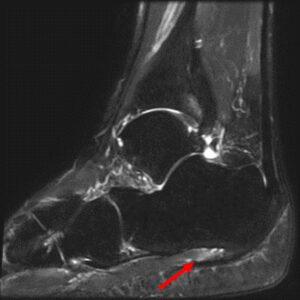

・超音波検査:足底腱膜の肥厚や炎症の有無を検査

・MRI検査:難治例や他疾患の鑑別が必要な場合に実施